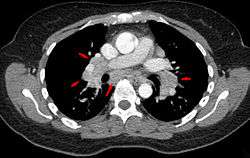

Hilar adenopathy especially on the person's left (coronal CT)

Hilar adenopathy especially on the person's left (transverse CT)